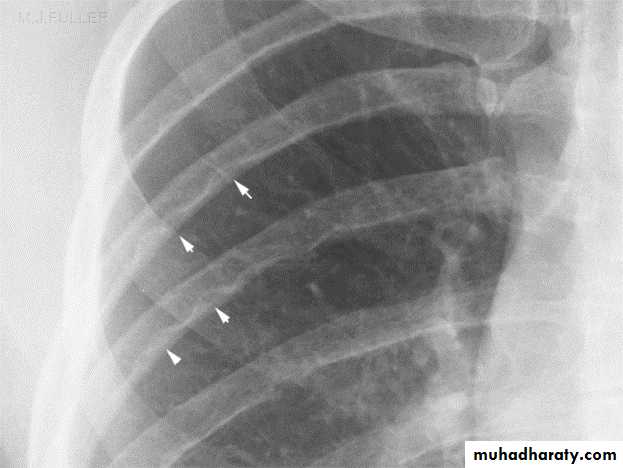

Investigations

In infantile type ECG and CXR show right ventricular hypertrophy with cardiomegaly and pulmonary edema while in older children they show left ventricular hypertrophy and a mildly enlarged heartIn older children(>8 years) the chest x-ray film may show notching

of the ribs due to the development of collaterals.